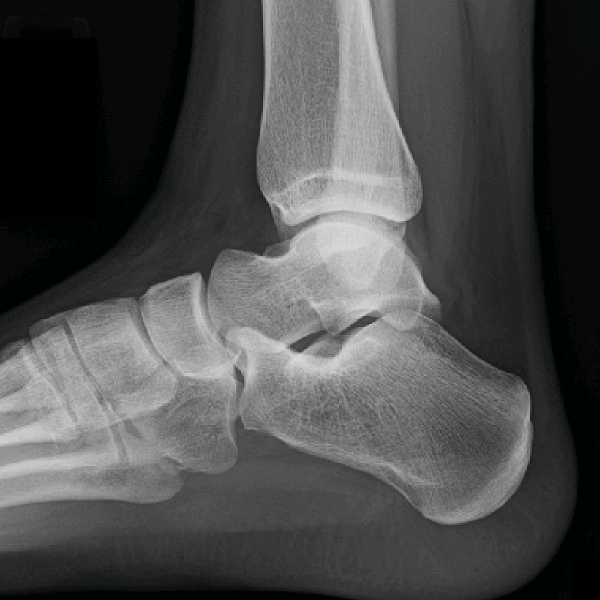

Learn the bony anatomy then test yourself